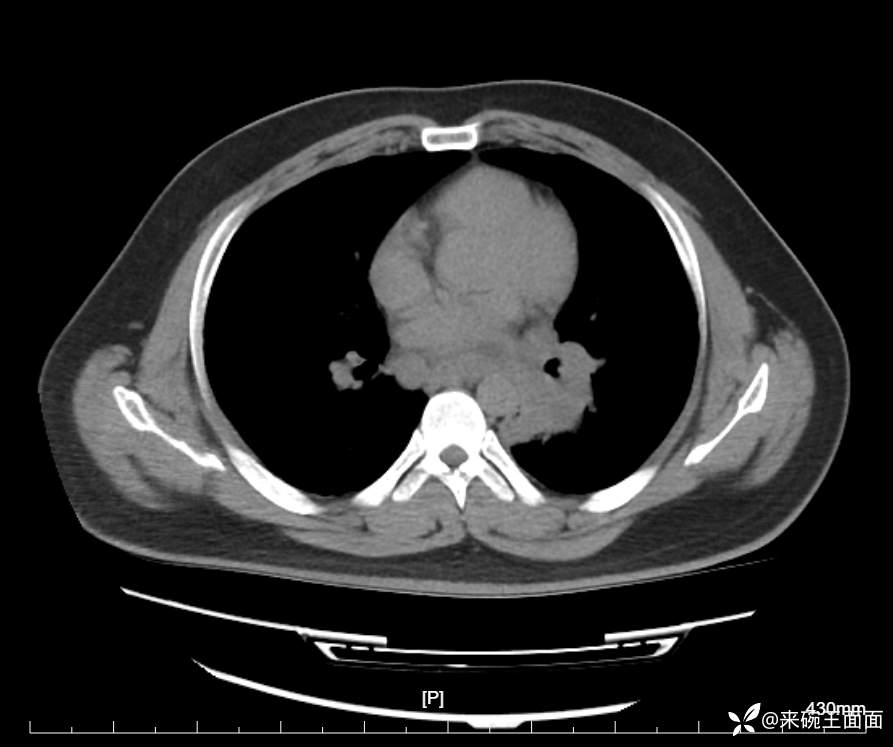

性别:男

年龄:27岁

主诉:胸闷胸痛数月余,休息后可自行缓解,无咯血症状。

个人史:数年吸烟史,具体不详。